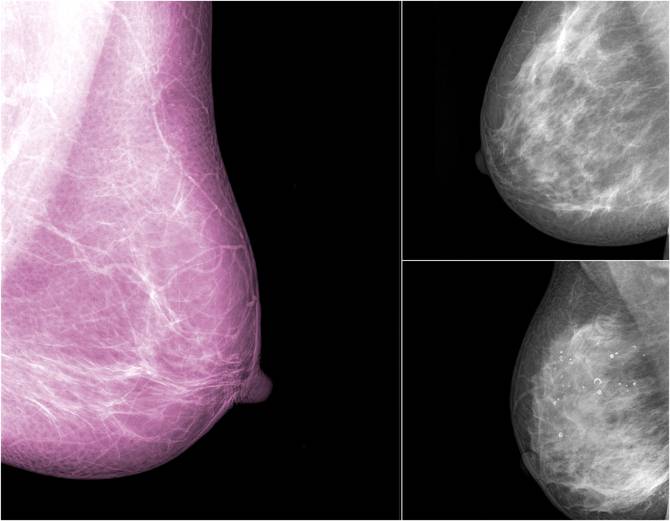

Cancro al seno: la densità del seno influisce sui rischi (FOTO)

valeria bellagamba

Care unimammme, il nostro seno cambia nel tempo, in funzione del tessuto ghiandolare. Le donne giovani hanno un seno più denso ...